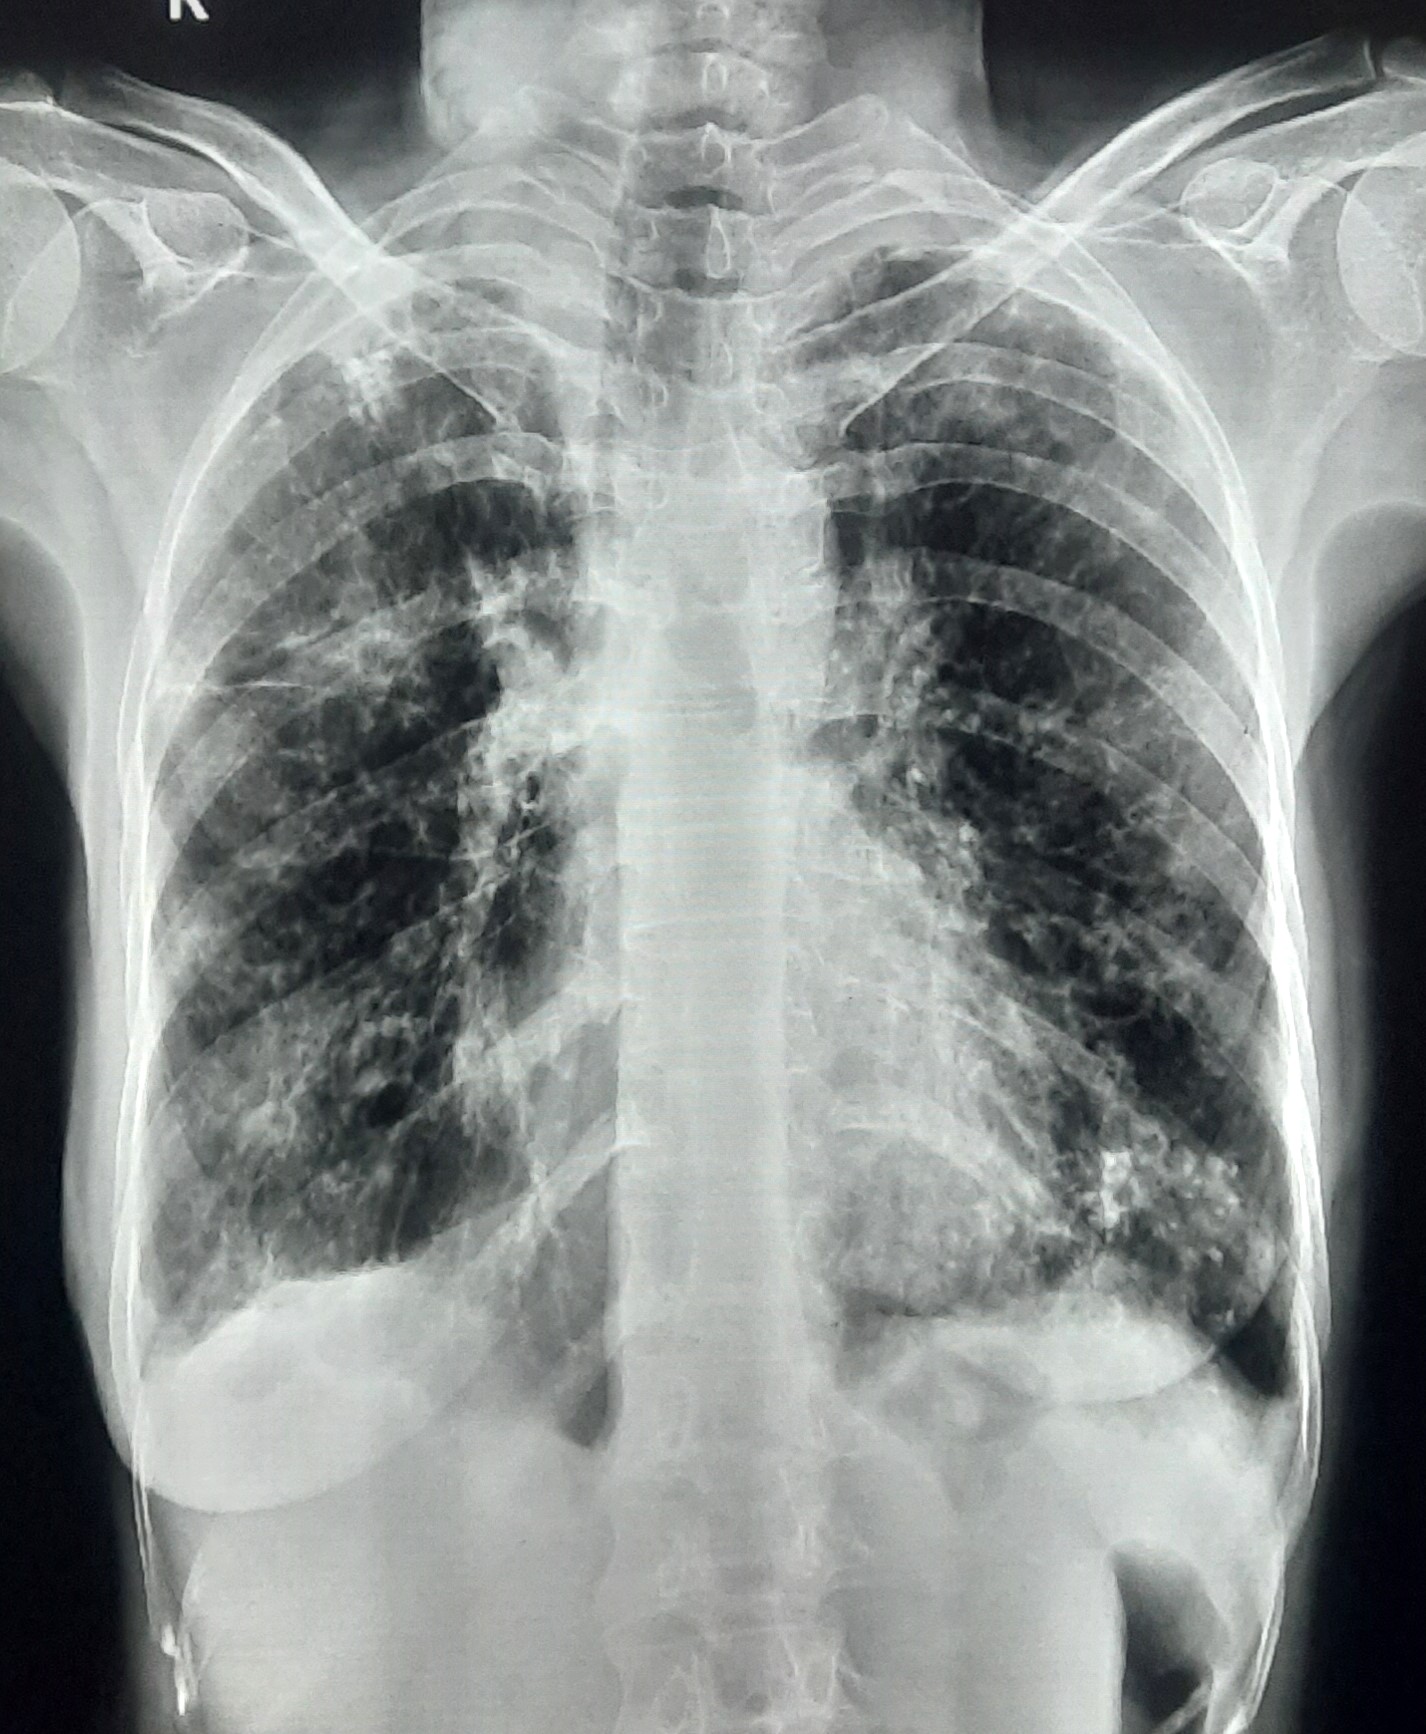

| 123 | IGGMC, Nagpur, Nagpur | P2 | 29-4349 | Dhammadip Wasnik | Consent taken on Paper | 35 Yrs. |

Provisional Diag : PTB Follow-up

Final Diag : Pulmonary Tuberculosis (Microbiologically Confirmed PTB) |

TB Case (Confirmed) | Abnormality visible on x-ray |